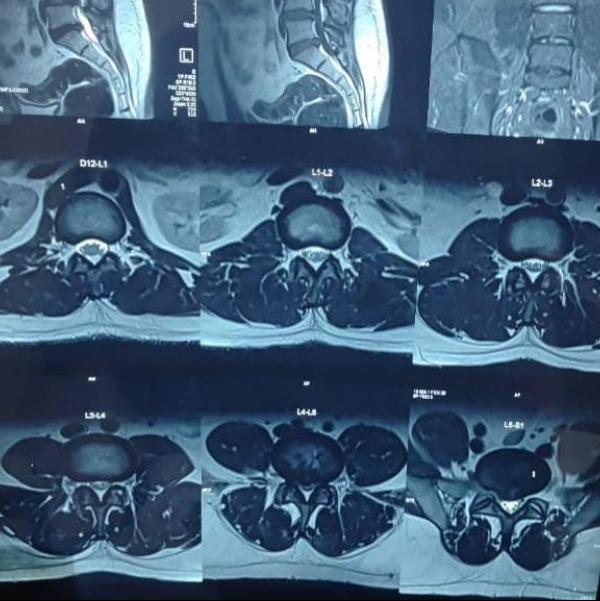

L4-5 ,L5-S1 PID with Bilateral LL radiculopathy with bilateral EHL,EDL weakness with Bladder involve...